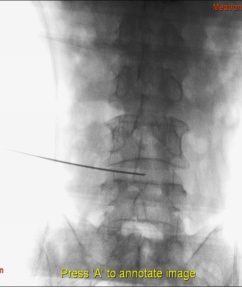

(1)患者采用俯卧位,提前设置好O型臂多维外科成像系统所需扫描定位平面(图1,图2),在正位透视下标定一条腰椎棘突中线,再沿髂棘最高点做一水平线,腰5骶1椎间盘正侧位的透视交叉点,即为穿刺点,一般在中心线旁开10-12cm左右处选一穿刺点。此线为穿刺的方向和角度(图3)。

图3 穿刺方向